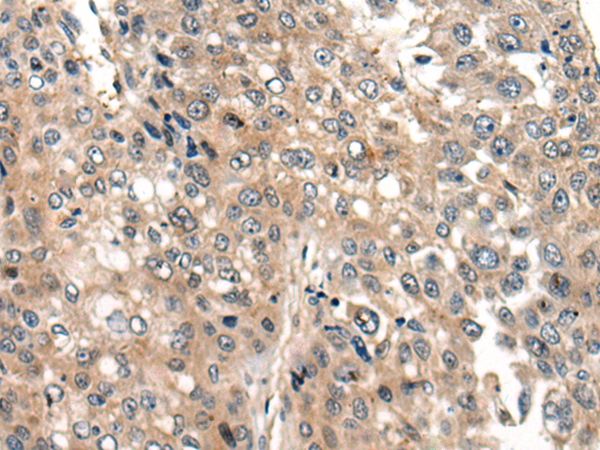

IHC positive control: |

Human liver cancer and human lung cancer |

IHC Recommend dilution: |

20-100 |